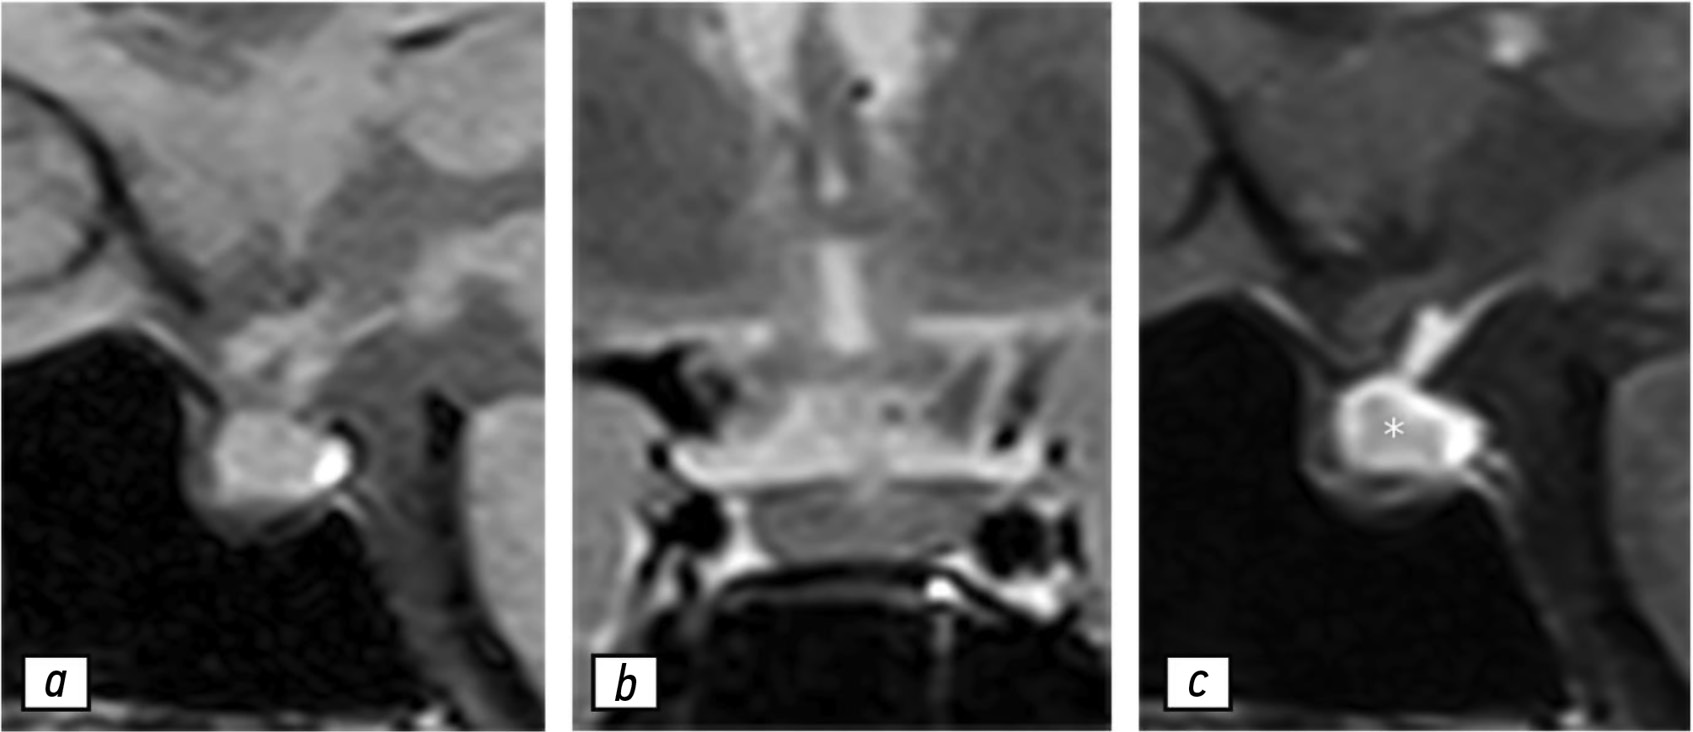

Magnetic resonance imaging in prenatal diagnosis of tuberous sclerosis complex: a case report

Early detection of orphan diseases, including tuberous sclerosis complex, requires a multidisciplinary approach and the integration of new prenatal diagnostic methods, utilizing ultrasound and magnetic resonance imaging. Accumulated knowledge of the clinical manifestations of tuberous sclerosis complex and advancements in diagnostic techniques enable the identification of this condition. Magnetic resonance imaging allows for high-quality anatomical and functional imaging of the brain in various planes, improving the sensitivity and diagnostic value of the method for early (prenatal) detection of cerebral manifestations of tuberous sclerosis complex. Additionally, magnetic resonance imaging detects mediastinal masses. This highlights the need for a comprehensive approach in diagnosing tuberous sclerosis complex, with magnetic resonance imaging as the primary method for assessing the fetus’s cardiovascular and central nervous systems.

This article presents a clinical case of tuberous sclerosis complex determined by intrauterine diagnosis followed by postnatal examination of the newborn and genetic confirmation of the diagnosis. This case report demonstrates the diagnostic value of magnetic resonance imaging in the prenatal diagnosis of tuberous sclerosis complex.

A 37-year-old female with a history of hyperprolactinemia was being treated symptomatically with cabergoline. At first magnetic resonance imaging heterogeneity of the hypophysis was revealed. In September 2021 the follow-up magnetic resonance imaging revealed an increase in the size and heterogeneity of the pituitary gland. In December 2021, the patient developed severe COVID-19-associated pneumonia and was treated with corticosteroids and oxygen support. In May 2022 magnetic resonance imaging revealed a marked increase in the size and heterogeneity of the pituitary gland. Significant clinical and radiological improvement were stated after adding prednisone (10 mg in the morning and 5 mg in the evening) to her treatment.

The patient was followed-up during the COVID-19 pandemic. The management and imaging studies of such patients may be tricky due to the effects related to COVID-19 and its treatment.

During monitoring of hypophysitis, physicians should consider the impact of COVID-19 treatment, particularly corticosteroid therapy, when evaluating the radiological changes.